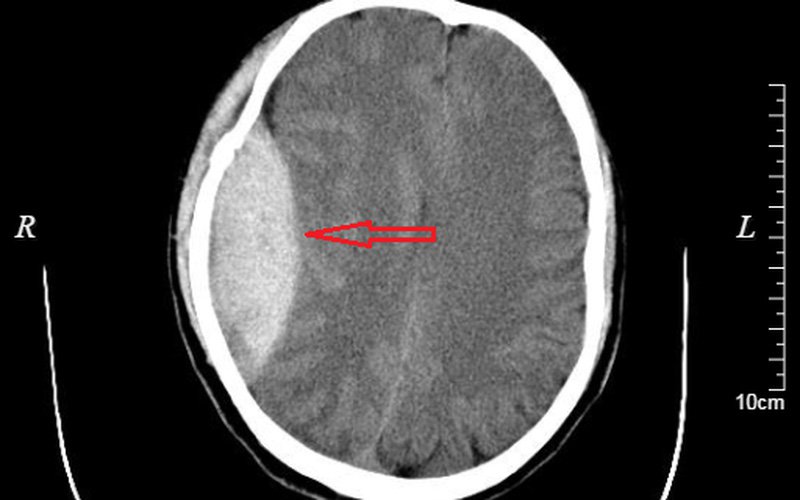

3. Các phương pháp chẩn đoán tụ máu dưới màng cứng

Những người chấn thương đầu thường được chụp cắt lớp vi tính (CT scan) hoặc chụp cộng hưởng từ (chụp MRI). Các xét nghiệm này tạo ra hình ảnh bên trong hộp sọ, giúp phát hiện bất kỳ khối máu tụ dưới màng cứng nào hiện diện.

MRI có ưu thế hơn CT một chút trong việc phát hiện máu tụ dưới màng cứng, nhưng CT nhanh hơn và sẵn có hơn.